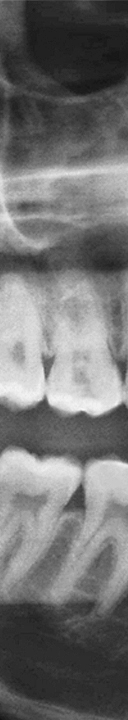

매복 사랑니의 경우 발치 시간도 많이 걸리고 주변 신경을 건드리지 않고 발치를 해야 하기 때문에 난이도가 있는 시술로 부작용이 생기지 않게 치료 받는 것이 중요하므로 신경 위치와 주변 치아의 상태를 정밀하게 검사 가능하고 숙련된 실력으로 사랑니 발치를 할 수 있는 의료진이 있는지 꼭 확인하신 후 치과를 선택하시기를 바라겠어요.

신논현역치과에서는 3D CT 장비로 촬영을 하여 사랑니의 매복 상태와 사랑니 부근의 신경처럼 중요한 부분을 정밀 검사를 통해 확인하고 사랑니 발치에 대한 안전한 치료 계획을 세운 후 발치를 진행하고 있었어요. 개인 구강의 상태에 따라 사랑니의 모양, 매복 형태 및 정도가 모두 다르기 때문에 아름드리에서는 그에 알맞는 방법으로 사랑니 발치를 환자 구강 상태에 맞게 진행하고 있었어요.